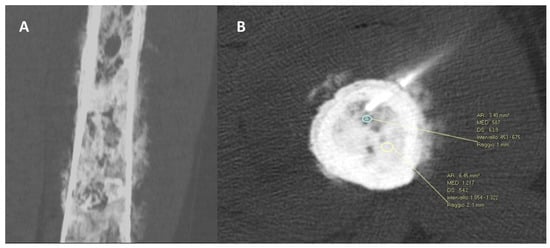

2.3. The Spine